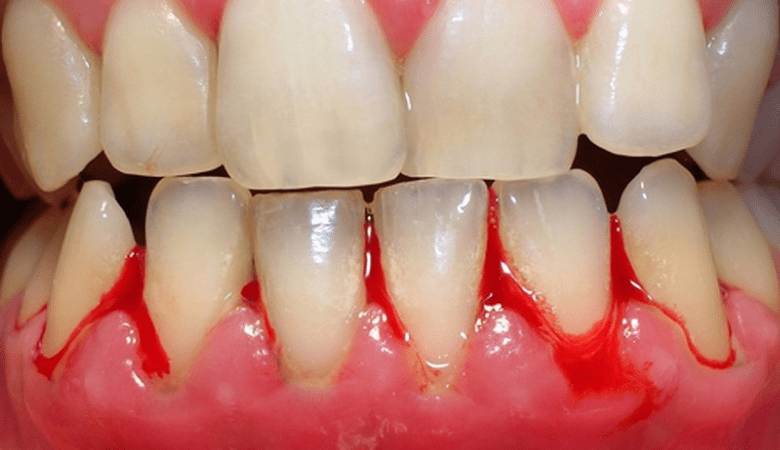

Viêm nướu răng gây chảy máu chân răng (Nguồn: Internet)

- Chảy máu nướu: Dễ bị chảy máu khi đánh răng, dùng chỉ nha khoa, hoặc có va chạm nhẹ.

- Nướu mềm và tụt khỏi chân răng: Nướu trở nên nhạy cảm, mềm yếu và có xu hướng tụt dần, để lộ chân răng.